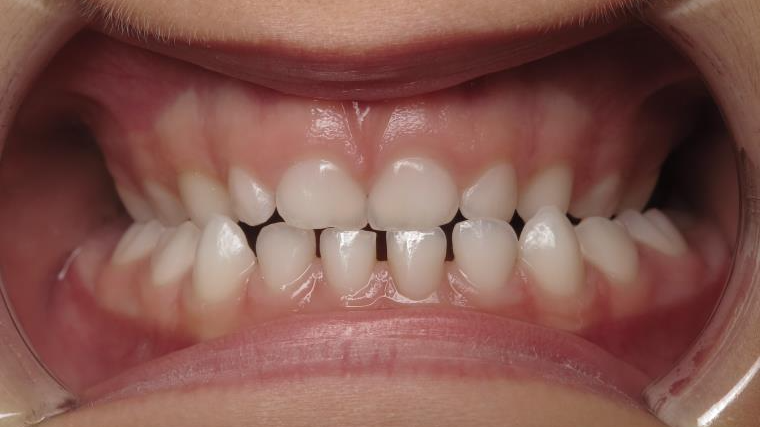

appareillage sectionnel multibagues pendant 18 mois

surveillance évolution de la dentition en cours

bilan début et en cours de traitement